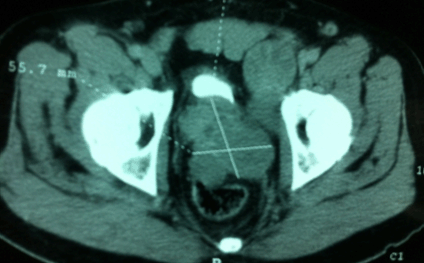

A computed tomography scan of the abdomen and pelvis revealed prostate tumor infiltrating the seminal vesicles, bladder base, rectum and a left iliac lymph node (Figure 1).

Figure 1: A pelvic computed tomography scan showing the prostate tumor infiltrating the seminal vesicles, bladder base and rectum with associated left internal iliac lymphadenopathy.